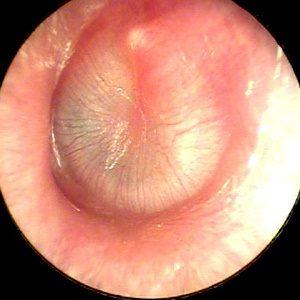

Врачи подчеркивают, что острый отит часто проявляется резкой болью в ухе, повышением температуры и ухудшением слуха. Для его выявления необходимо провести осмотр уха с помощью отоскопа, что позволяет оценить состояние барабанной перепонки. Важно также учитывать сопутствующие симптомы, такие как насморк или кашель, которые могут указывать на вирусную инфекцию.

Врач, принимая во внимание жалобы пациента, проводит осмотр ушного канала с использованием отоскопа и, при необходимости, назначает: